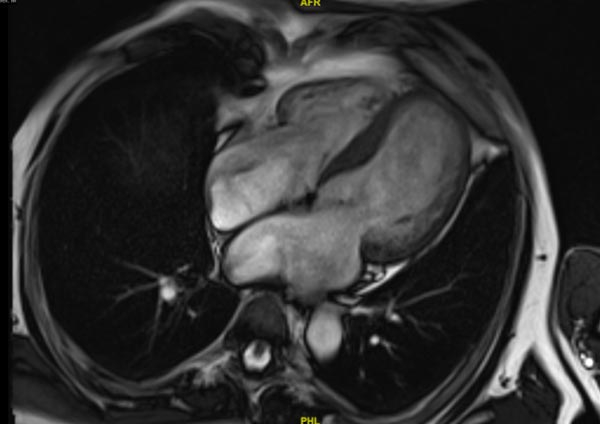

IRM cardiaque

- FEVG mesurée à 30 %.

- Les volumes indexés sont mesurés à 86 ml/m² en télédiastole et 62 ml/m² en télésystole

- Hypertrophie au niveau septale avec SIV à 13-14 mm

- L’étude de rehaussement tardif met en évidence une prise de contraste intra myocardique au niveau du septum

Figure 2

Vidéo 4 : Argus Ventricule gauche

Vidéo 5 : Ciné Truefisp 4 cavités

Vidéo 6 : Tfi Psir single shot 8sl petit axe Psir

Vidéo 7 : Tfi Psir single shot 8sl 4 cavités Psir